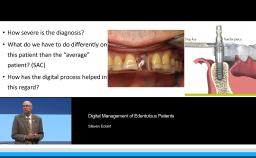

This lecture presents a concept for choosing the type of reconstruction and material for highly esthetic outcomes. Due to the number of restorative possibilities, the selection of an ‘ideal’ material is getting more and more complex. Advantages of all-ceramic materials over traditional metal-ceramics include their tooth-like color and their enamel-like translucency. The main limitation of ceramics is their brittleness, leading to a risk for fracture during clinical service. This lecture discusses the development of modern ceramics with increased stability to reduce this risk, with a focus on high-strength ceramic zirconia and its potential as an alternative to metal. For the processing of zirconia, numerous computer-aided manufacturing procedures are available today. Moreover, multiple clinical studies show promising results for zirconia-based tooth and implant reconstructions.